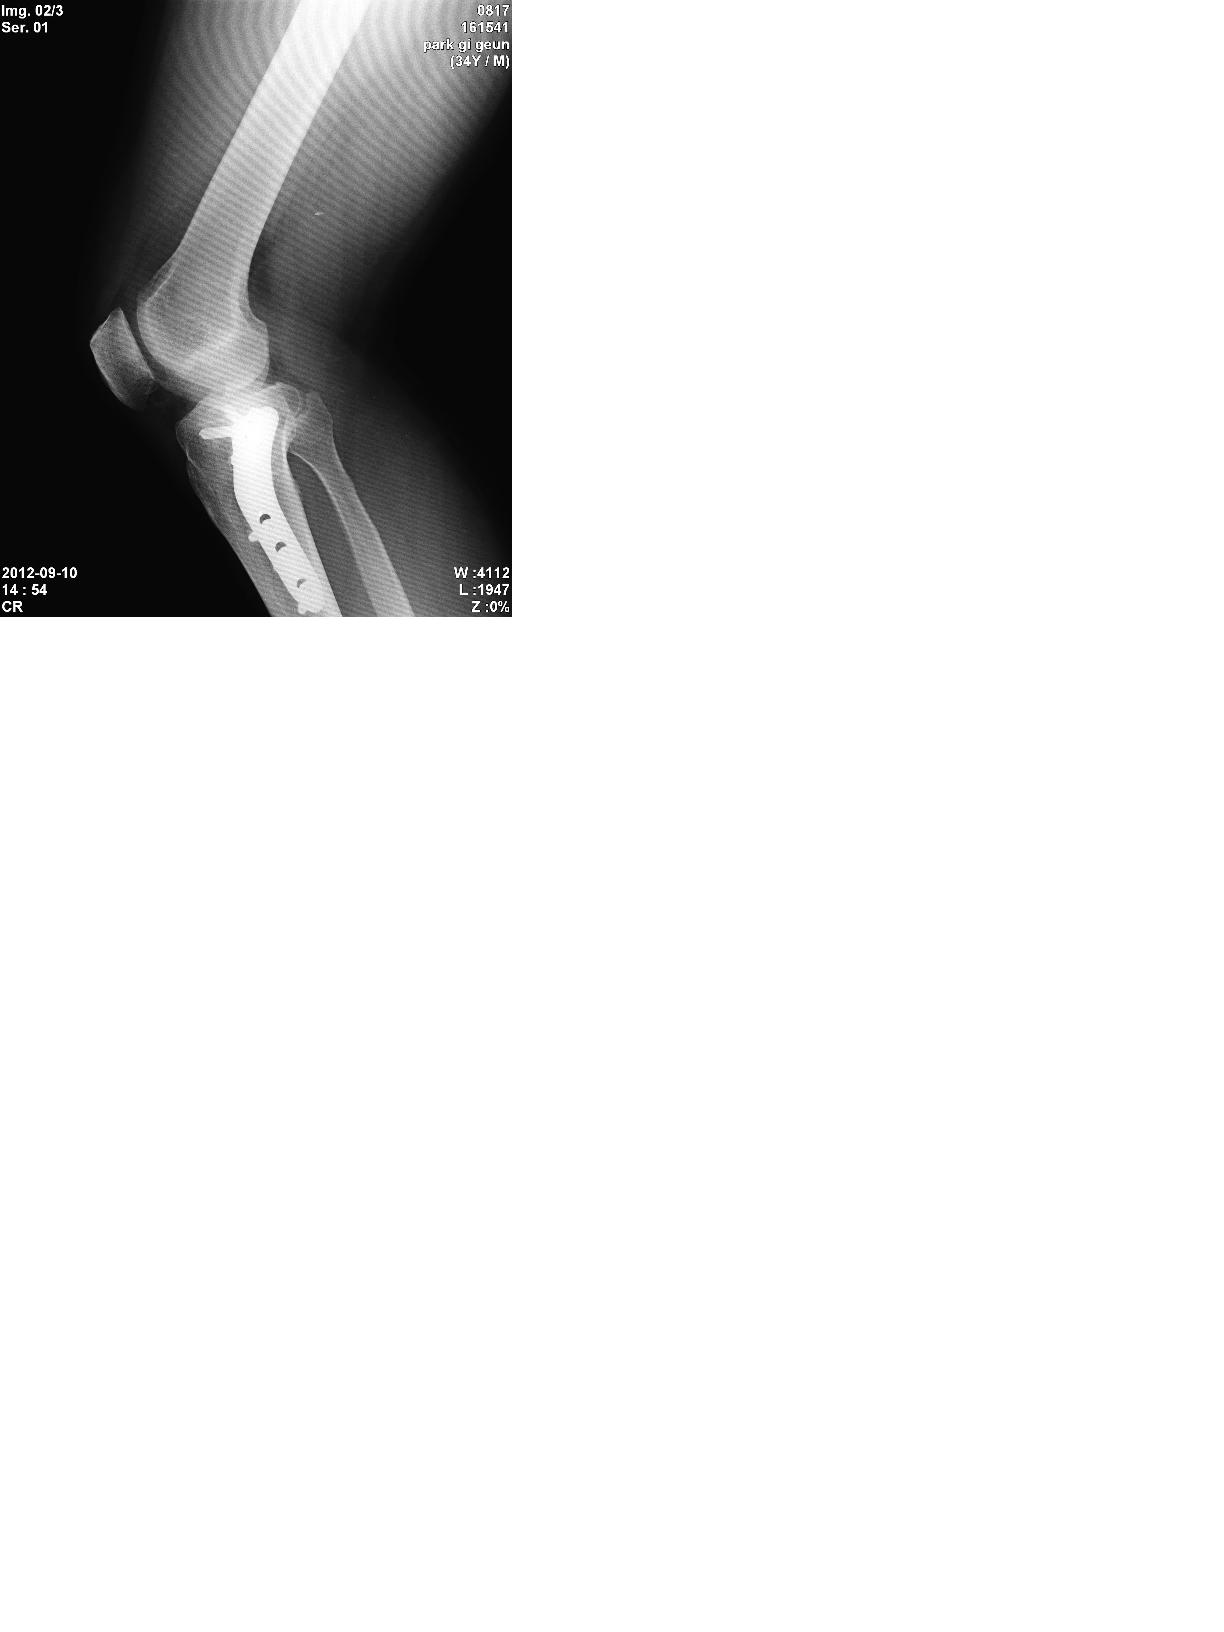

2005년 사고로 연골 떠받드는 부위에 금이가서 핀 고정술을 하였습니다

약간의 관절 강직으로 보행은 무리가 없으나 달리기와 점프 그리고 다 접히지 않는 관절 강직이 좀 있어요

장애 나올까요? ㅎㅎ  수술한 대학병원 교수님은 자존심때문인지 운동 좀더 합시다 이러는데 ㅡㅡ 5개월 넘개 재활 했는데 다 안구부려집니다 ㅠㅠ

전문가들의 답변을 기다립니다 ㅎ'제목 없음3.JPG 제목 없음1.JPG 제목 없음2.JPG

X-ray